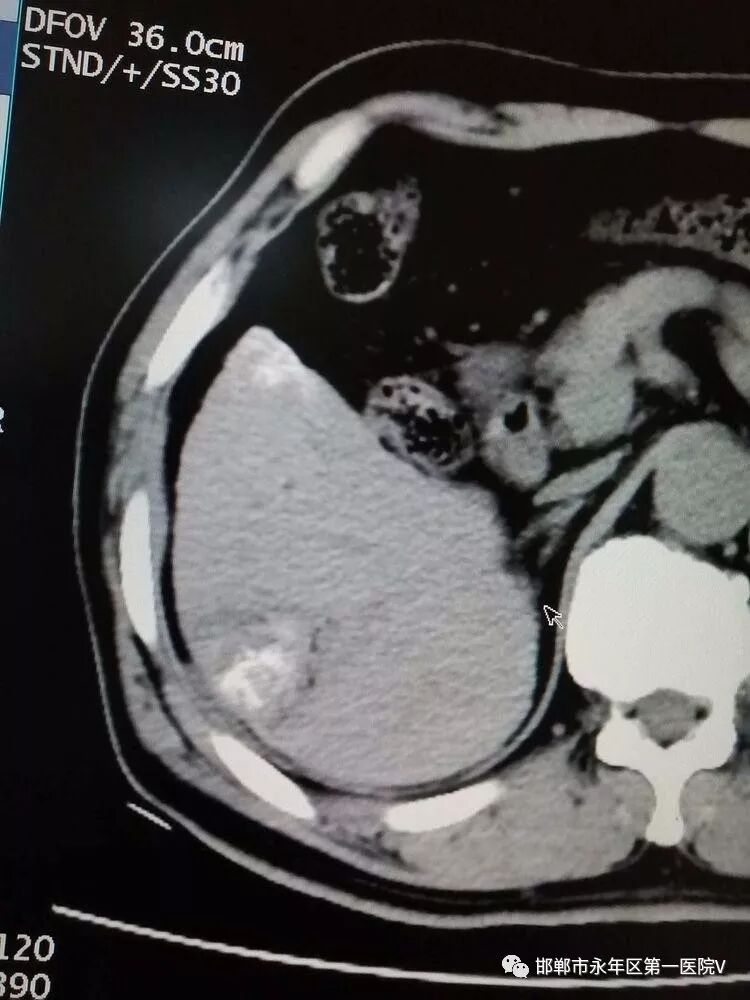

患者赵某,男,67岁,肝硬化病史4年,常规复查发现肝占位,约2.2*2.5cm,上腹部CT、MRI平扫及其增强均符合原发性肝癌典型表现,诊断明确!依据2017年中国原发性肝癌诊疗规范,肿瘤分期属|a期,根治性治疗可选择手术切除或者消融,永年区第一医院肝内科王书芳主任和家属充分沟通后,患者选择消融治疗!

2019年10月19日在CT室行CT引导下原发性肝癌射频消融术!术中射频消融针精确穿刺到肿瘤中心,并展开子针包绕肿瘤并扩大消融范围,加热至90℃持续消融约10分钟。感谢CT室同事们的大力支持及积极的配合!

行2次叠加消融达到完全根治肿瘤的目的,术后扫描可见肿瘤完全坏死及周边安全范围低密度晕,手术成功!!!